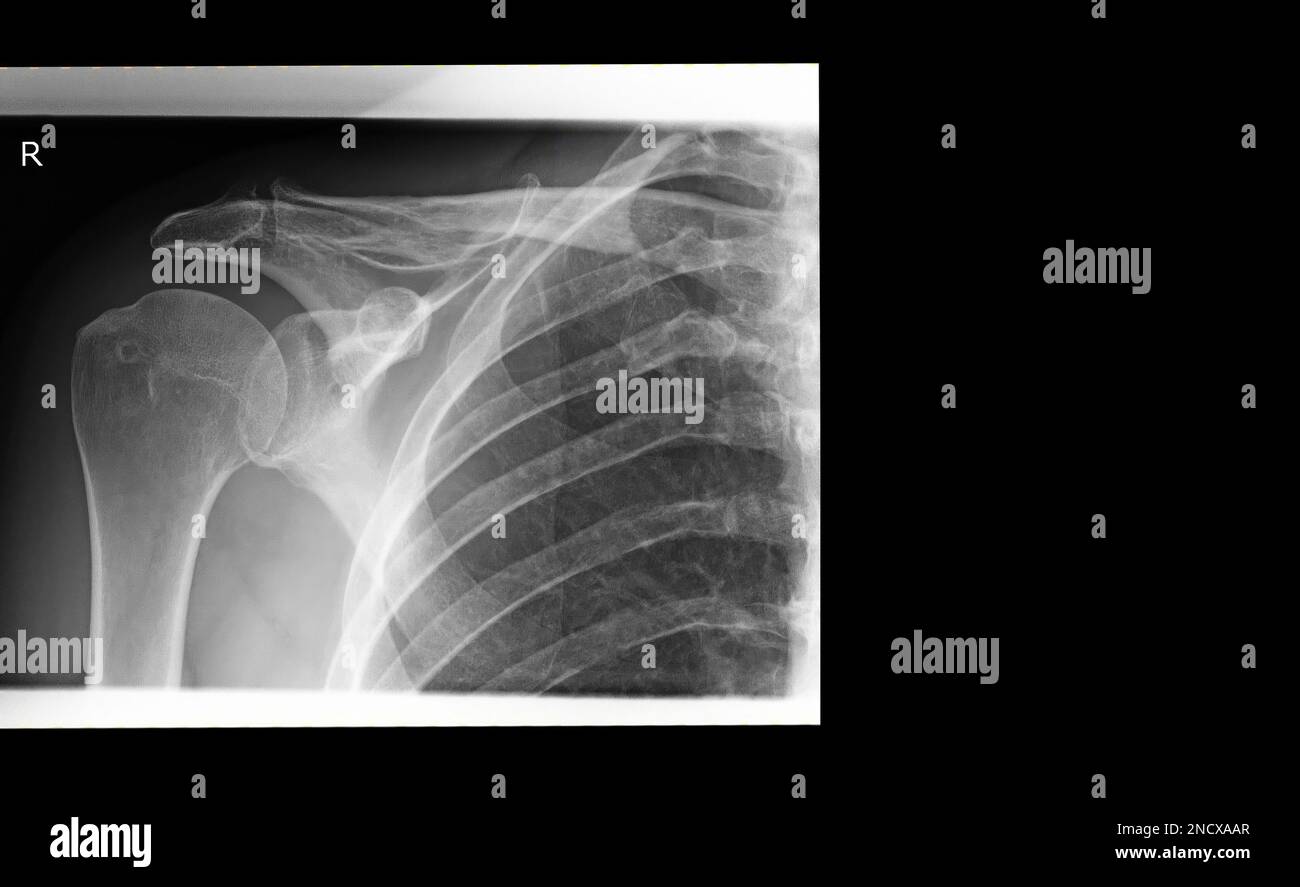

Xray image of a shoulder joint Stock Photo Alamy Shoulder X Ray Ac Joint Right shoulder anatomy with ac ligaments. Occurs via direct trauma to the adducted shoulder. The view optimizes visualization of the acromioclavicular joint, as overlying structures can limit. The acromioclavicular (ac) joint radiographic series is used to evaluate the acromioclavicular joint and the distal clavicle. The zanca view is used in the assessment of acute and chronic acromioclavicular joint injuries. Loss. Shoulder X Ray Ac Joint.

Normal shoulder joint, Xray Stock Photo Alamy Shoulder X Ray Ac Joint The view optimizes visualization of the acromioclavicular joint, as overlying structures can limit. The zanca view is used in the assessment of acute and chronic acromioclavicular joint injuries. Right shoulder anatomy with ac ligaments. The ac joint (a) connects the clavicle to the scapula and suspends the. The acromioclavicular (ac) joint radiographic series is used to evaluate the acromioclavicular joint. Shoulder X Ray Ac Joint.